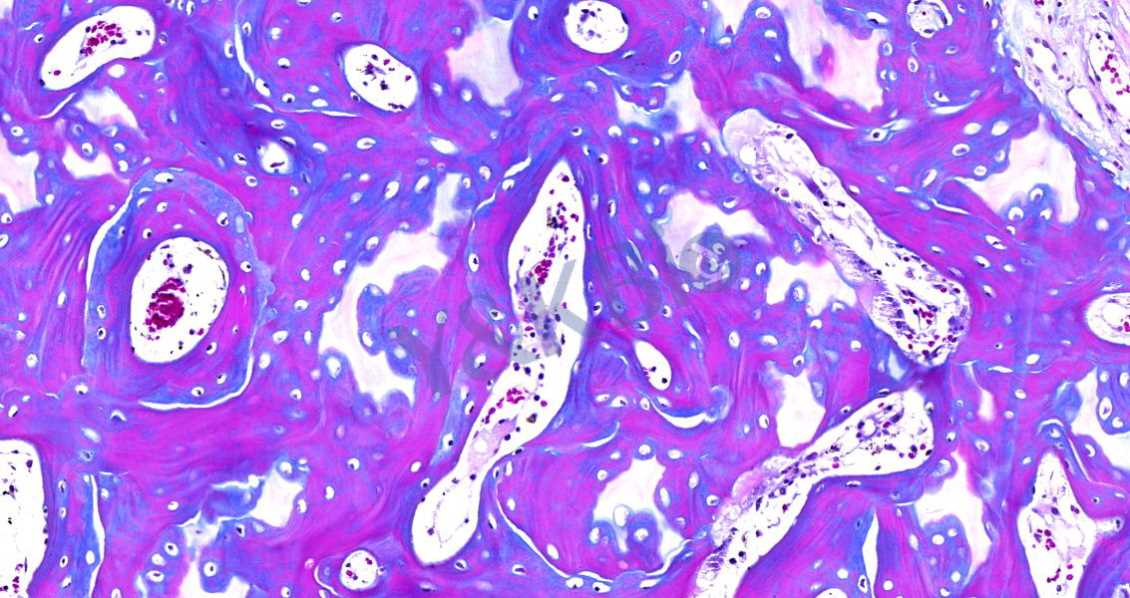

Masson染色的颜色对比鲜明,可见明显的胶原纤维网(黑龙江苯胺蓝染色则为蓝色,甲基绿则为绿色),能较好地反映纤维组织的形态。其中,蓝色表示新形成的骨,红色表示成熟的骨组织。

3.番红O-固绿染色

番红O-固绿染色可直观反映关节软骨、软骨下的骨组织结构,嗜碱性的软骨与碱性染料番红 O 结合呈现红色,嗜酸性的骨和酸性染料固绿结合而成蓝色,在关节软骨及软骨下骨的形态学研究中受到了欢迎。